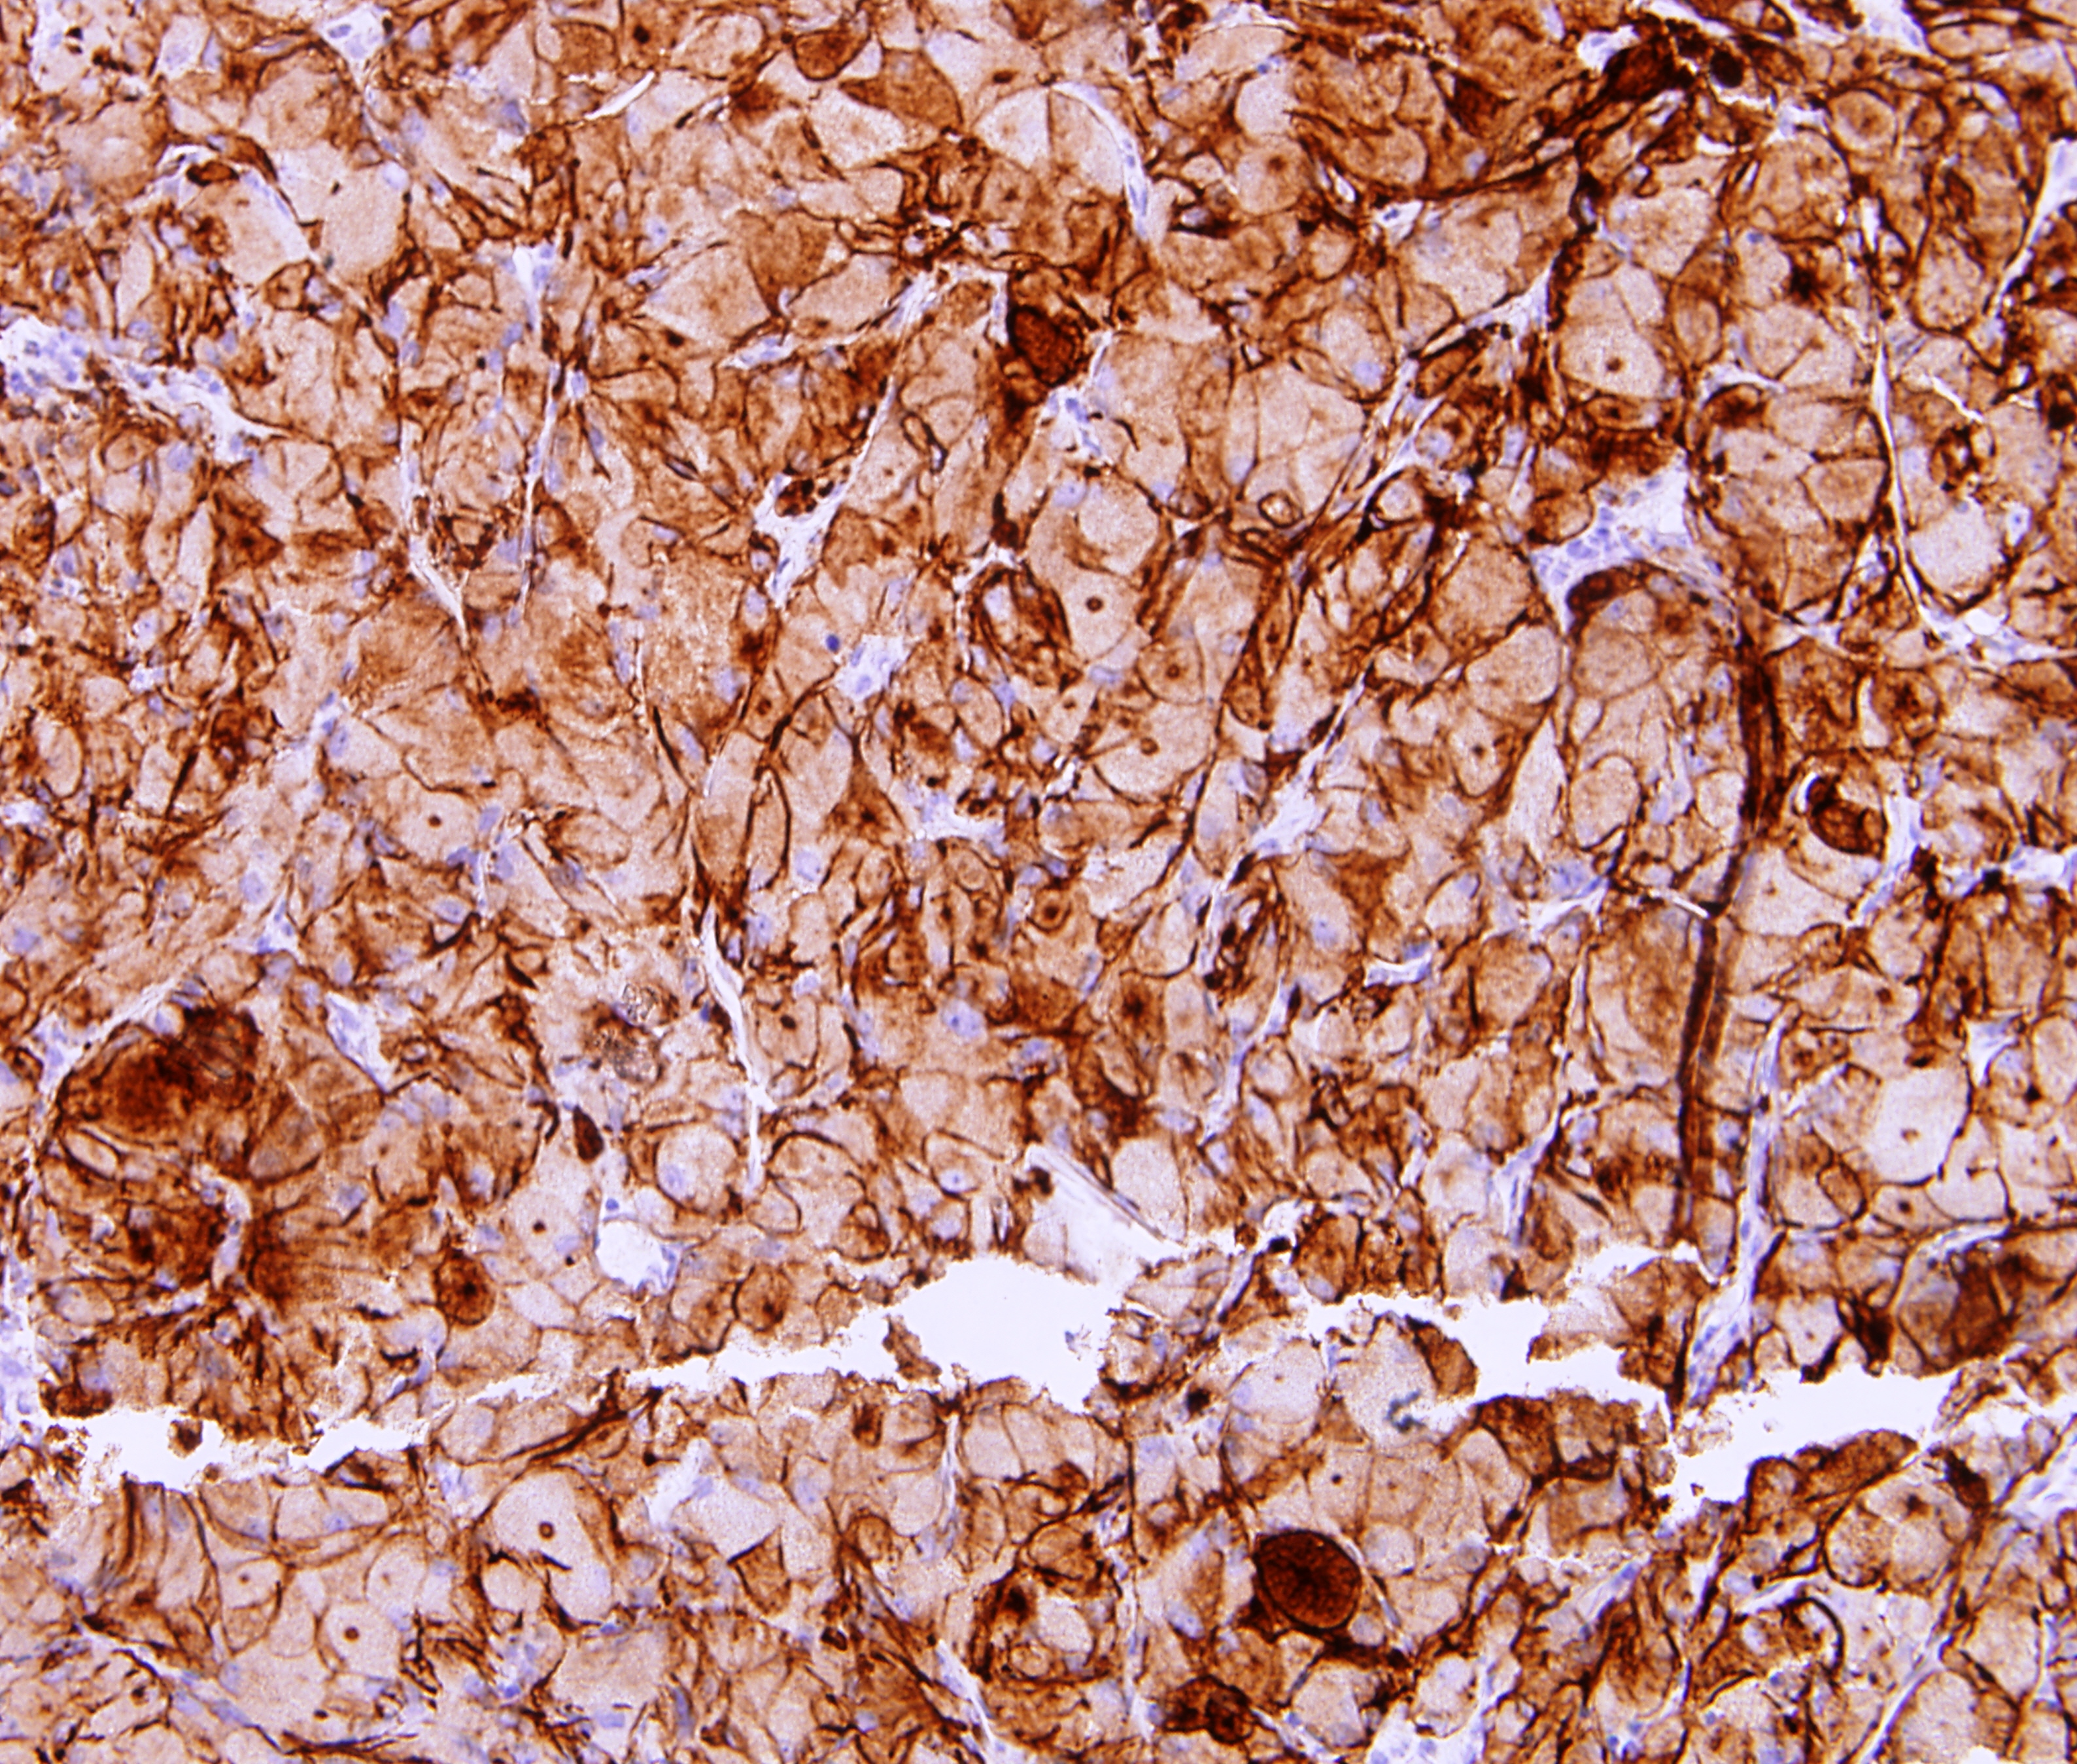

| 4. | Descripción | Resumen | Introducción. Es un tumor benigno muy infrecuente, supraselar y/o intraselar, que se origina en la neurohipófisis o en el infundíbulo. Se presenta habitualmente en la edad adulta, con mayor incidencia en mujeres. No existen síntomas o signos específicos que permitan distinguirlo de otras lesiones supraselares, aunque la diabetes insípida es relativamente infrecuente. El diagnostico final es generalmente a través de la anatomía patológica donde se constatan células con citoplasma granular eosinófilo, debido a la presencia de abundantes lisosomas. Estos tumores son immunonegativos para todas las hormonas de la hipófisis anterior, de variable positividad para la proteína S-100, y por lo general negativos para la proteína gliofibrilar ácida (GFAP). La resonancia magnética suele mostrar una lesión supraselar bien circunscrita, con captación homogénea o heterogénea de contraste. La cirugía es el tratamiento de elección. Objetivo. Dar a conocer la presencia de este tumor en nuestro medio. Material y método. Paciente de femenina de 48 años de edad, que ingresa por alteraciones del campo visual (hemianopsia bitemporal) y cefalea holocraneal.En el examen físico se constata papiledema bilateral. Resultado y discusión. Se concluye el caso como un tumor de células granulares de la neurohipofisis, y se compara con el reportado en la literatura. |

Cd 68 (27KB) laminas histologica proteina acida gliofibrilar ( GFAP ) (4MB) hematoxilina y eosina (5MB) S-100 (6MB) RMN de hipofisis (62KB) |